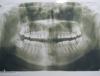

Хомячишко Опубликовано 26 июня, 2013 Поделиться Опубликовано 26 июня, 2013 (изменено) Добрый день . Прошу дать совет в моей ситуации . 25 лет . На верхней челюсти зуб 12 вырос вторым рядом за клыком . Имеется смещение осевого центра ( верх челюсти ) т е центр приходится посередине одного из передних зубов . Ортодонт предложил 2 варианта устраниния : первый: удалить18 , 28 , 38 и носить брэкеты даймон на обеих челюстях при наиблагоприятнейшем развитии событий носить 2 года + каждые 1,5-2 мес на осмотр . Второй вариант - удалить 12 и сделать косметическую реставрацию 13 , 11 и 21 ( как я понимаю пломбировочным материалом ) . Первый вариант не устраивает из-за длительности ношения брэкетов , второй устроил когда был на приеме но из-за того , что не был поставлен в курс о его минусах . Мой лечащий стоматолог (не ортодонт ) также крайне не рекомендовал мне второй вариант . Хотелось бы еще услышать мнения от компетентных специалистов . Снимки пригагаю . Благодарю заранее Изменено 26 июня, 2013 пользователем Хомячишко Ссылка на комментарий

Salma Опубликовано 3 июля, 2013 Поделиться Опубликовано 3 июля, 2013 пожалуйста ответьте надо решить уже что-топомимо неправильного положения второго резца , на фото отмечается сужение зубных рядов, скученность на нижней челюсти, решать конечно вам, но ортодонтическое лечение вам показано.Я не знаю какой вид реставрации вам предложили, наверное виниры из пломбировочного композита, такие реставрации не очень то долговечные, часто быстро теряют приличный внешний вид, из за чего нуждаются в периодической переделке, для их изготовления препарируется передняя поверхность зуба на мм или больше Ссылка на комментарий